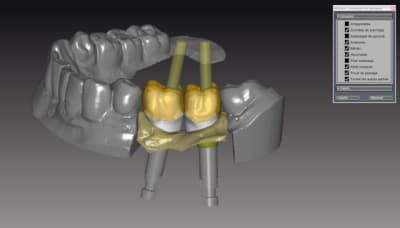

donc voici comme promis piliers ZR sur base Titan

passivité total de l'armature , les piliers sont tous réglés , parallélisés lors de la modélisation de l'ensemble . l'usinage des piliers et de l'armature ce fait séparement pour encore qualité d'ajustage..

Dans le ce cas present Strauman BL 3.3 rc

collage des base titan avec du multilink automix

ce cas est en cour de réalisation , essayage de l'ensemble

déja validé ... je n ai pas de eu de photos , aucun blanchiment de gencive , merci l'ajustage des profils d'émergence dans le soft qui est vraiment bien fait ..

*

a suivre..

je m'éclate vraiment avec les possibilitées qu'offrent le system d'usinage ...

Pour l'instant 100% de client satisfait pourvu que ca dure....